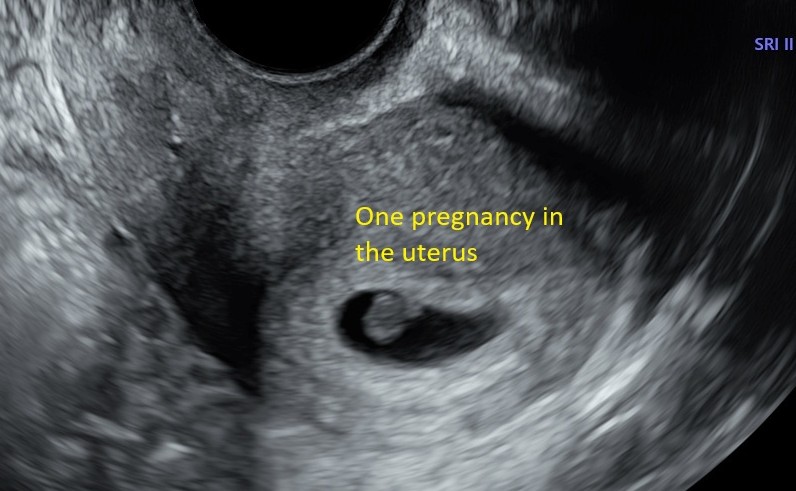

CORRECT POSITION:

If your baby is in the correct place - this being inside of the uterus - (a pregnancy outside of the uterus is called an ectopic pregnancy and can be dangerous)